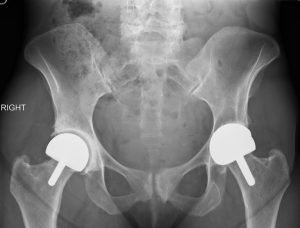

It is possible to safely make acetabular implants with 4 mm of polyethylene, 2 mm of metal backing, and 1 mm of porous coating (29,30) (Figure 1). This ensemble still can have an effective polyethylene liner locking mechanism. If the construct were any thinner it would need to be one piece, as it could not accept a locking mechanism for the polyethylene liner. A two-piece implant allows the use of a central threaded impactor which affords better visualization during insertion. Impactors for one-piece implants can impede visualization and or require a more complex inserter (27). Also, a two-piece implant allows for independent polyethylene exchange and for supplemental screw fixation if necessary.

Polyethylene wear with liner sizes up to 52.5 mm has been shown to be minimal both in clinical application and in wear simulator studies up to 30 million cycles (18). The wear experienced with hip resurfacing parallels the favorable wear seen with total hip replacement. However, edge loading from impingement is still a concern. The solution has been to use polyethylene fully supported by the acetabular shell (Figure 1). There are two acetabular polyethylene designs that have been used for resurfacing in which the polyethylene liner covers the edge of the metal backing leaving a vulnerability to impingement of the femoral neck against the polyethylene (26,27). The wear of highly cross-linked polyethylene has been studied using wear simulation, clinical retrievals, and by imaging using computed tomographic (CT) scans. All three methods suggest low wear equating to a lifetime of use.